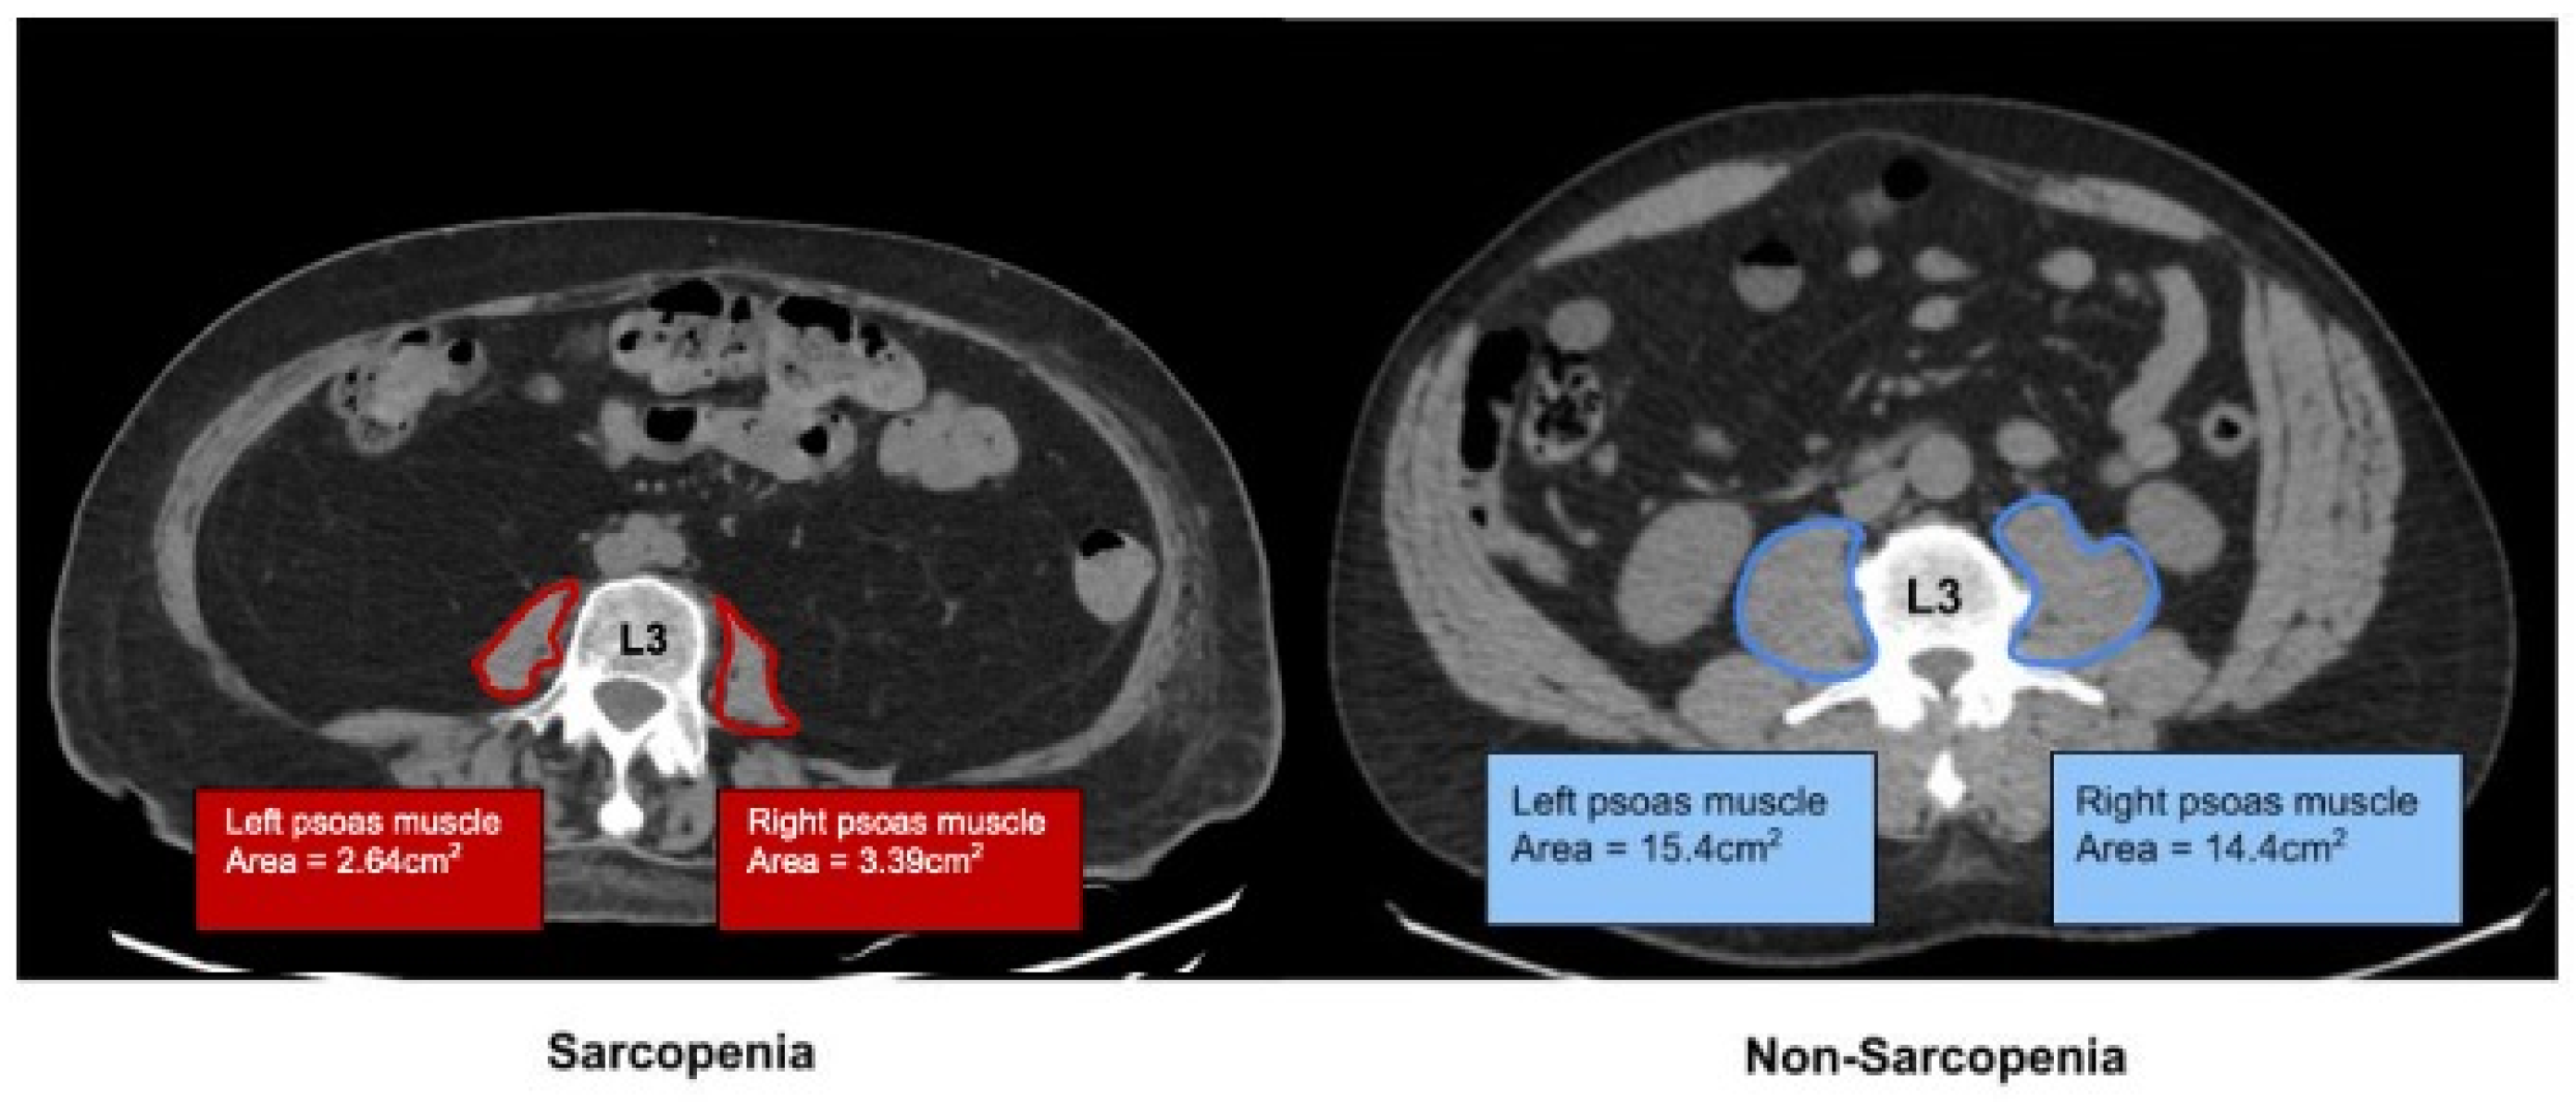

2.1. Determination of Sarcopenia by Imaging

| PMI | Psoas Muscle Index |

- Bahat, G.; Turkmen, B.O.; Aliyev, S.; Catikkas, N.M.; Bakir, B.; Karan, M.A. Cut-off values of skeletal muscle index and psoas muscle index at L3 vertebra level by computerized tomography to assess low muscle mass. Clin. Nutr. 2021, 40, 4360–4365. [Google Scholar] [CrossRef]

| Psoas Muscle Index (PMI) | 5.22 (±2.87) | 3.24 (±0.75) | 6.11 (±1.18) | <0.001 | |